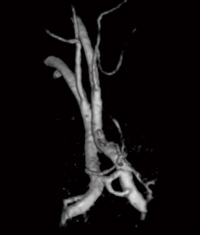

日立メディコの1.5T MRI装置は,このような検査に対応できる十分なポテンシャルを備えている。図1は,右中大脳動脈に動脈瘤,あるいは狭窄があった場合の撮像方法(b),ならびに得られたVR(volume rendering)画像(a)である。空間分解能は0.6mm isotropic dataで対象血管だけのin-flow効果を最大に得るためにサジタルの設定でねらう方法である。

図1 右中大脳動脈の高精細MRA

また,前大脳動脈,前交通動脈部も動脈瘤の好発部位である。図2は,前大脳動脈をターゲットとした高精細MRAの撮像方法(b),ならびにMIP画像(a)である。これもサジタルの設定で,内頸動脈にスラブが重ならないようにスライス枚数(スラブ厚)を設定することがコツである。また,MIPだけでなくVR処理をすることによって,前交通動脈の構造をより正確に観察することができ,動脈瘤の診断に非常に有効とされている(図3)。

図2 前大脳動脈の高精細MRA

図3 前大脳動脈の高精細MRA(VR)